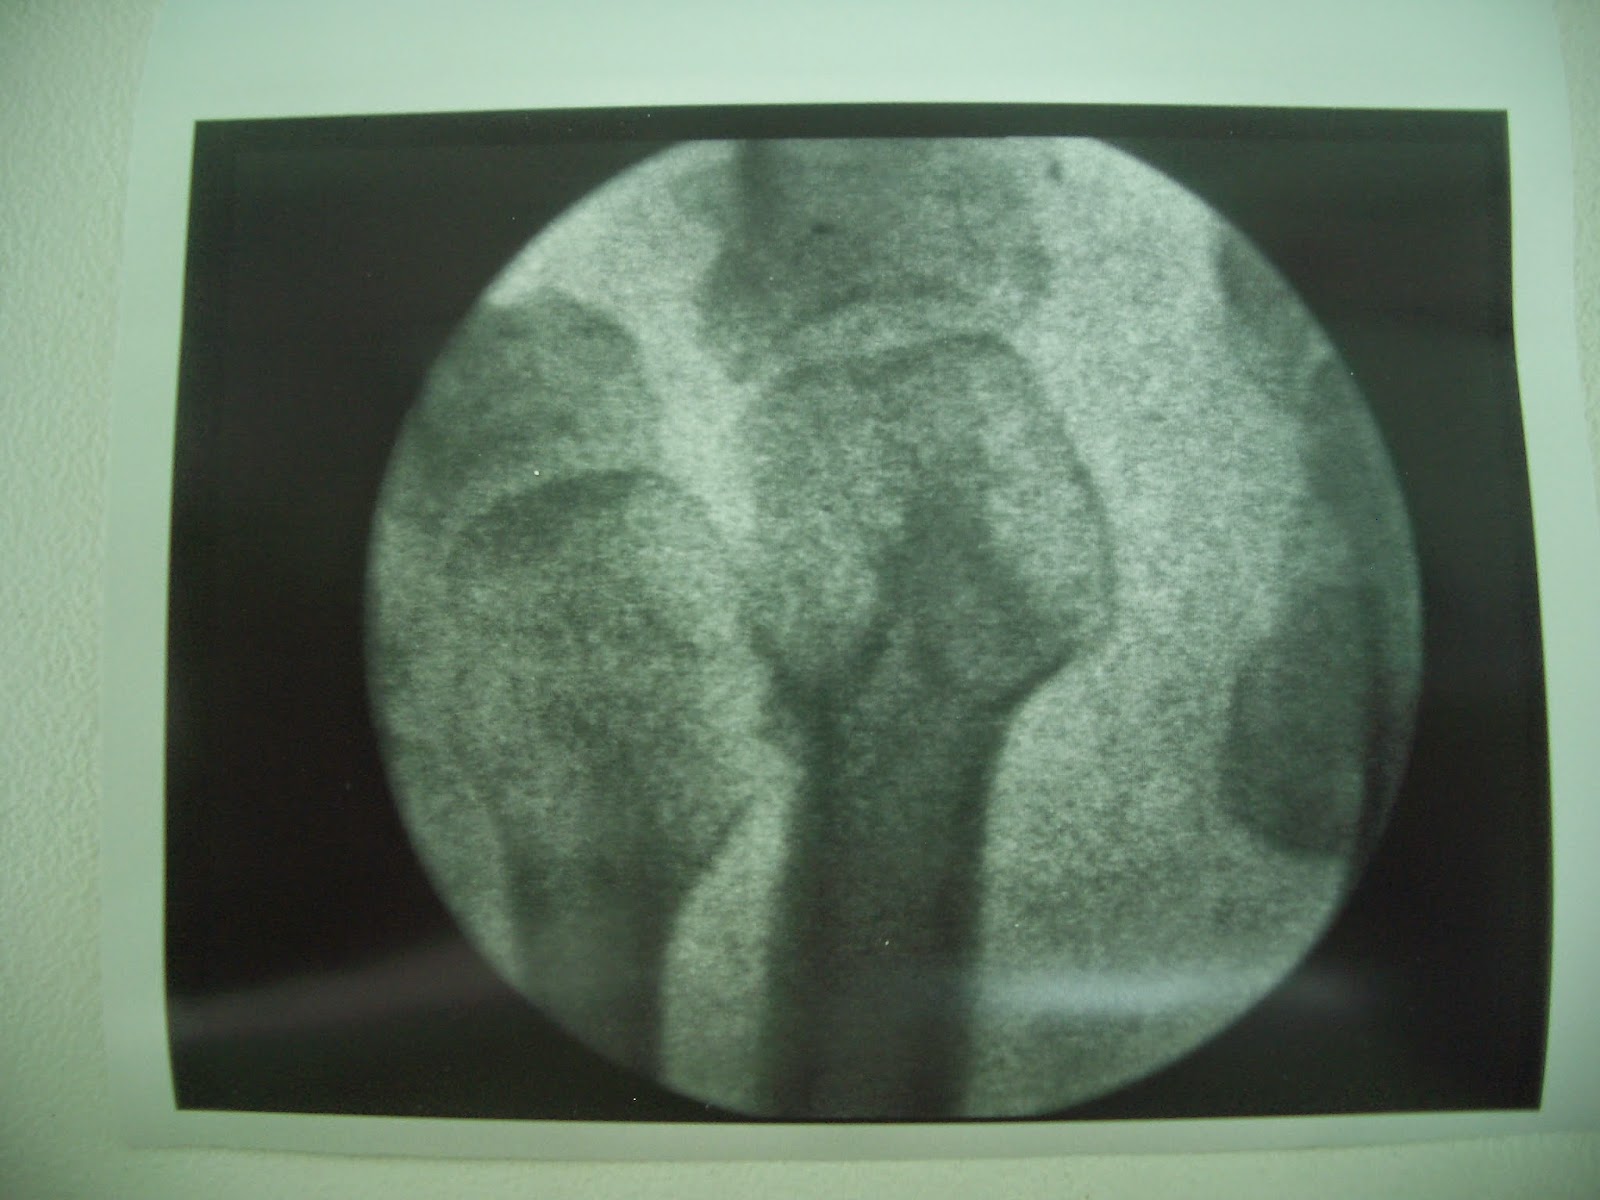

Otro caso para mi precioso. Paciente a la que operé hace unos cuatro meses de una sobrecarga metatarsal. Le realicé una osteotomía en V en la cabeza del segundo metatarsiano como se puede ver en la imagen de la foto de la izquierda.

A día de hoy, cuatro meses después, se puede ver la osteotomía en V totalmente osificada y la paciente fenomenal, sin dolores.